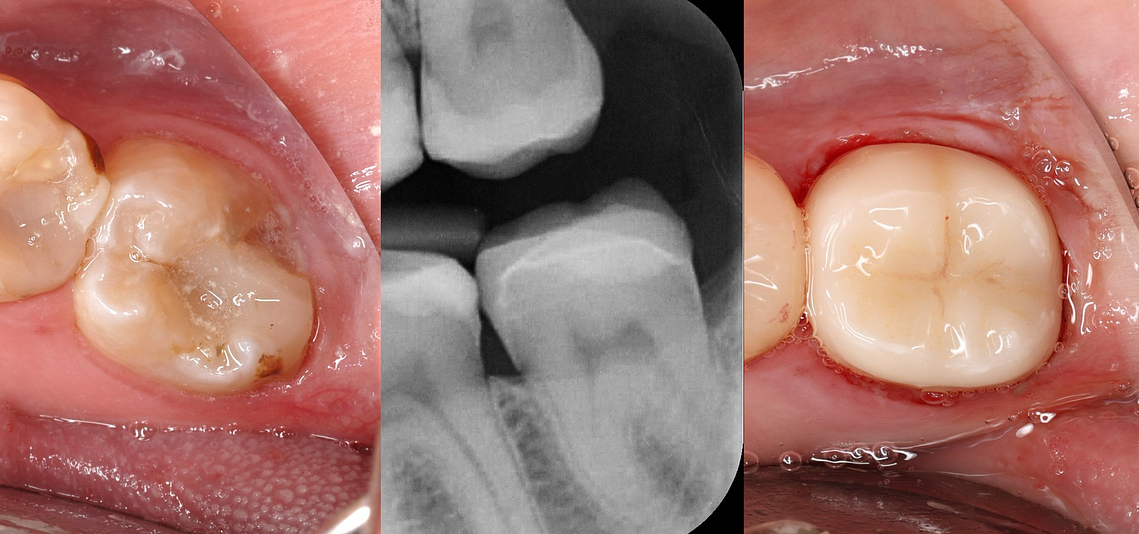

Here you can see the final milled crown, which we made from IPS EMAX CAD ceramic.

This was then post processed, cut off the sprue, stained, glazed, and put it in a furnace. And you can delegate this to the team. We then can resin bond this onto our tooth preparation. And yes, with adequate minimum thickness, this can be used on a second molar.

This is the final result. All carried out in a single visit.